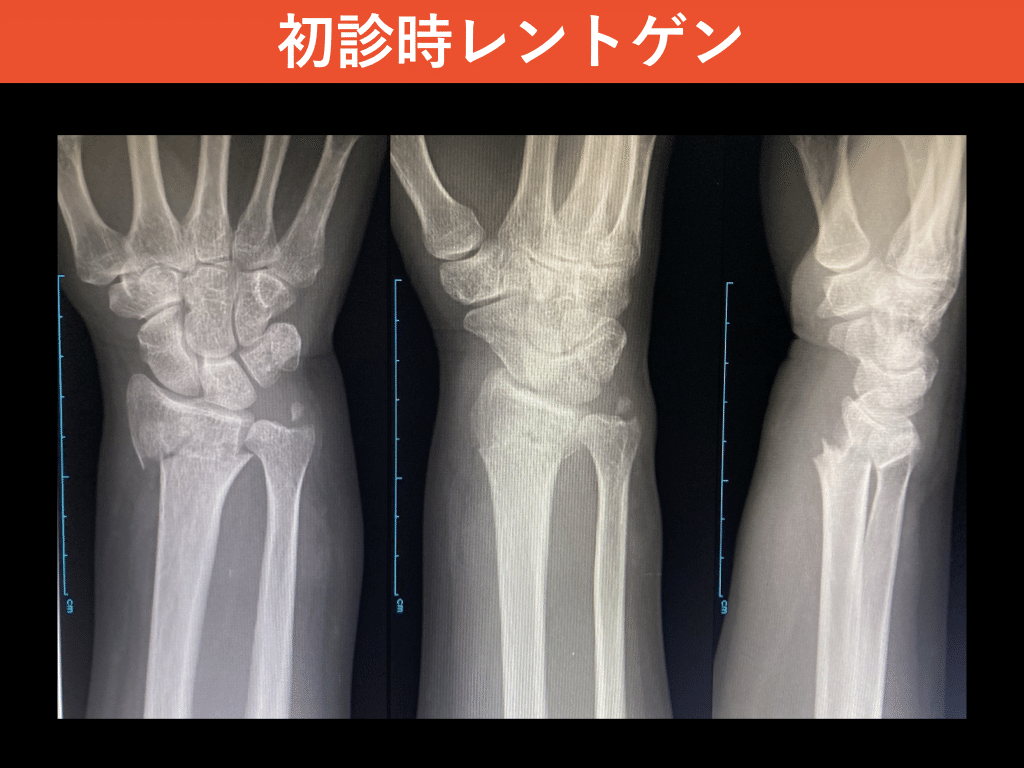

HOT ! ★裁断なし★ 【新版】 橈骨遠位端骨折 金原出版

金原出版。☆裁断なし☆ 【新版】 橈骨遠位端骨折。☆裁断なし☆ 【新版】 橈骨遠位端骨折。所属する当院に出品予定なので、お譲りいたします。購入後、数ページを一度開いた程度なので状態は◎です。症例報告:橈骨遠位端骨折(AO分類:C2)」#書く習慣152|整形外科で。マーカー文字記載なし。。BLSプロバイダーマニュアル AHAガイドライン2020準拠 新品未使用。編 集森谷 浩治 / 依田 拓也定 価12,100円(税込)

• ☆裁断なし☆ 【新版】 橈骨遠位端骨折

• 症例報告:橈骨遠位端骨折(AO分類:C2)」#書く習慣152|整形外科で